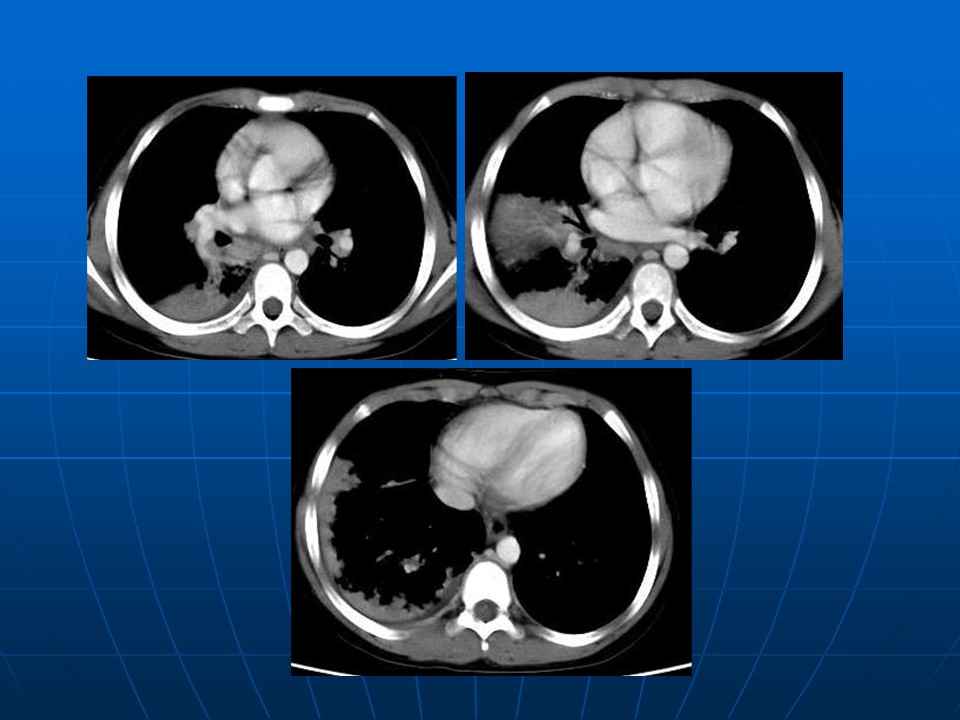

【PPT】早期肺癌易漏诊征象分析